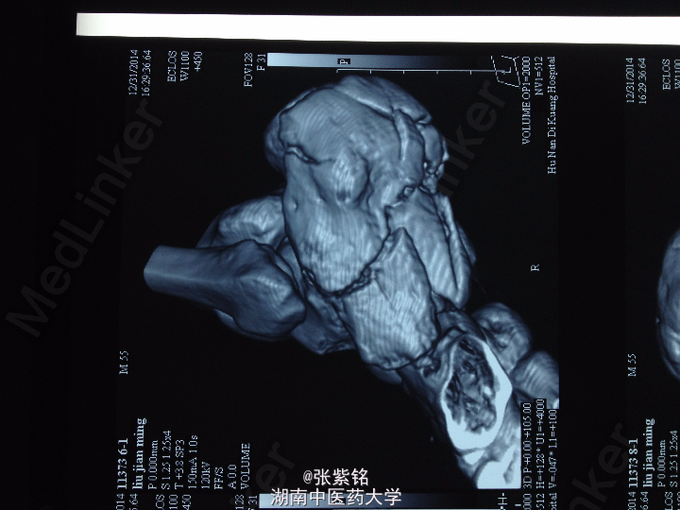

查体:左足部肿胀明显,可见大面积皮下青紫瘀斑,压痛明显,尤以足跟部为甚,左足跟部可扪及明显骨擦音,足踝关节主动活动受限,被动活动疼痛明显加重,左足背动脉搏动可扪及,伤肢血运感觉可。 辅查:左足正斜位片示:左跟骨骨折。 左足CT平扫+三维重建:左跟骨骨质连续性中断,可见多发骨折线,骨折端对位对线不良,并可见多块碎骨片,骨折线累积关节面,左足软组织明显肿胀;左跟骨粉碎性骨折。

诊断:左跟骨粉碎性骨折 处理:石膏外固定,切开复位钢板螺钉内固定术。 术后14日左足跟部切口处中段皮肤软组织坏死,切口未愈合,钢板螺钉外露,切口处感染。 细菌培养+药敏结果:凝固酶阴性葡萄球菌。 予以VSD切口处负压引流7日后拆除,行取皮植皮术,术后皮片坏死。